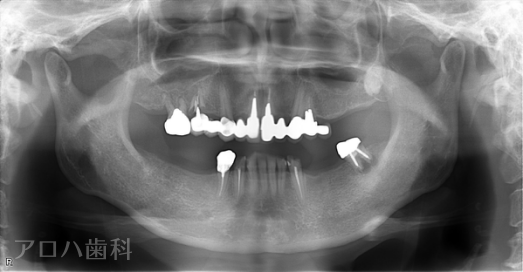

CASE01

初診時

治療終了後5年時

| 主訴 | 入れ歯をやり替えたい |

|---|---|

| 治療内容 | 上下顎とも状態が悪い歯を抜いて奥歯をインプラントで修復しました。 前歯は患者さまの希望のもとそのままにしています。 上顎は骨の高さが足りなかったため、【サイナスリフト】という特殊な手術を行い骨の高さを獲得しています。 術後経過もメインテナンスに通っていただいており、良好な状態を保っています。 |

| 治療期間 | 1年6ヶ月 |

| 治療費用 | 5,060,000円 |

| 費用詳細 | ・サイナスリフト(2か所) 660,000円 ・セデーション(静脈内鎮静法) 110,000円 ・TEC(仮歯) 220,000円 ・インプラント手術+アバットメント+上部構造(9歯) 3,960,000円 ・ポンティック(1歯) 110,000円 |